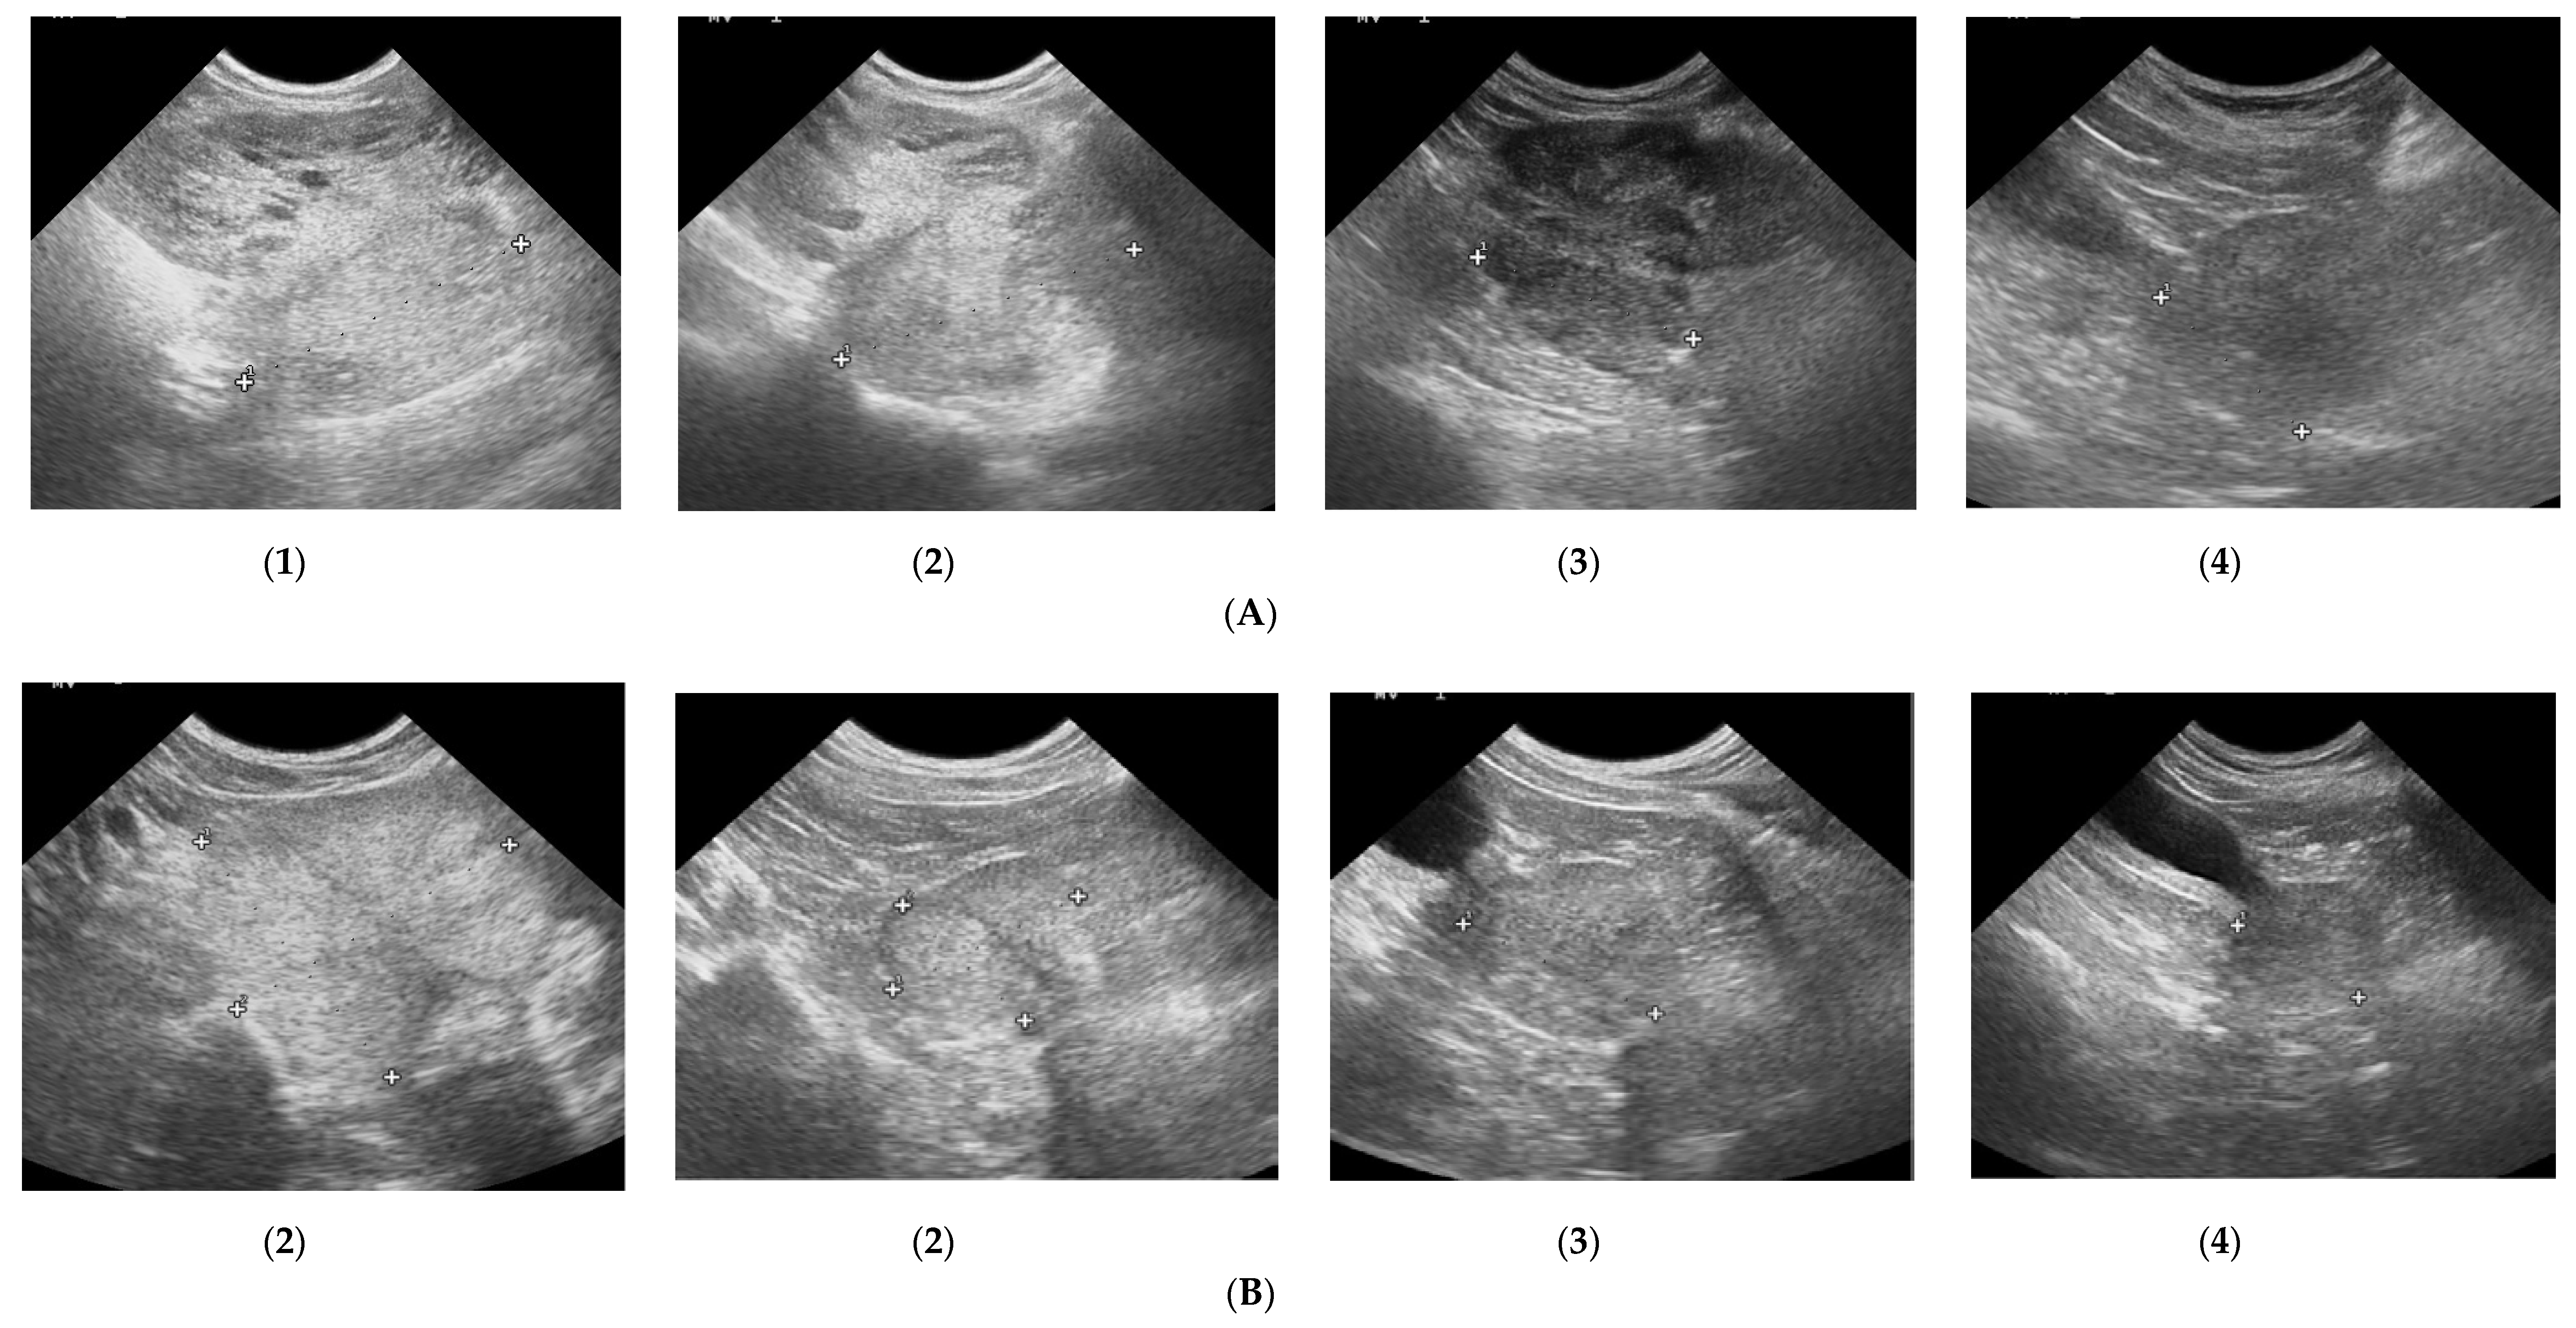

3.1. Prostate B-Mode Appearance

3.2. Doppler Ultrasonography of the Prostatic Artery